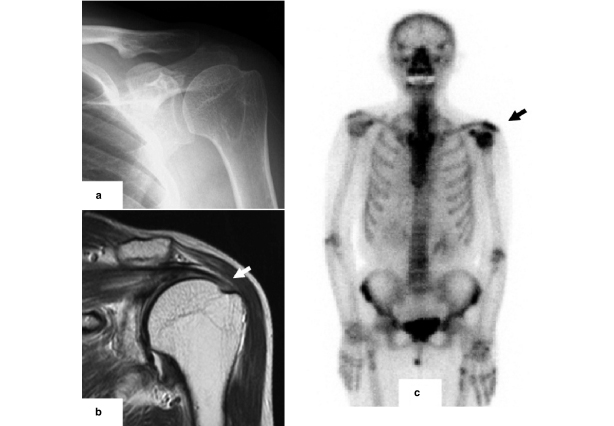

Image from OpenI – Licensed by CC